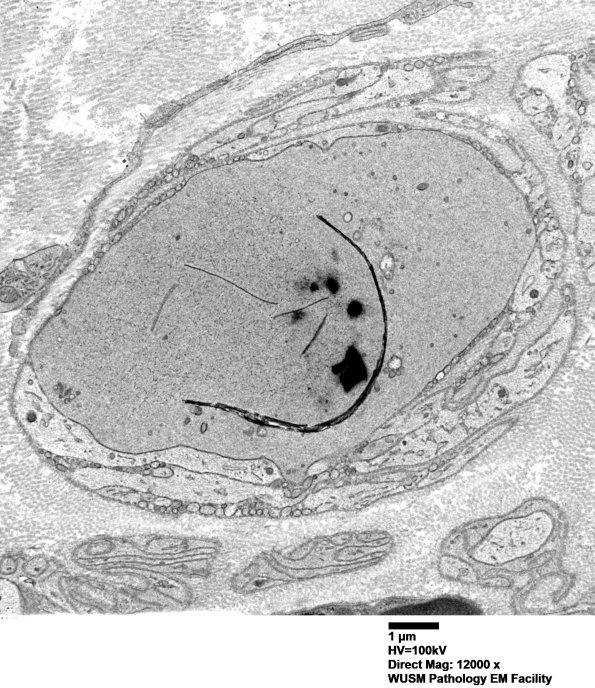

11R1,2 Shown is a large axon with dense axoplasm, tubulovesicular elements and a membranous cleft. (electron micrographs)